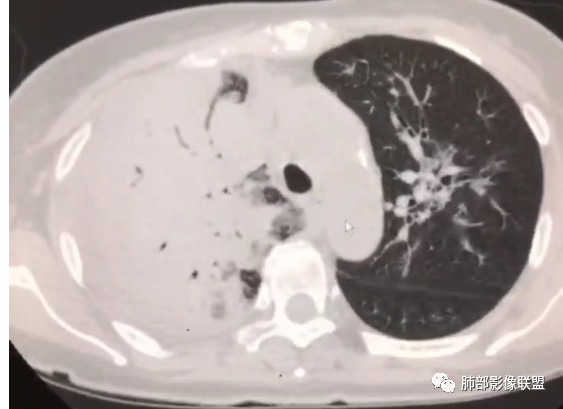

第二次CT:

首先考虑感染性病变,合并右侧胸腔积液,增强扫描强化明显,左侧也有少许感染,病变无坏死,可见支气管充气征,支气管镜上叶管腔狭窄,未见新生物。

右肺大叶实变,支气管扩张,有强化,胸腔积液考虑淋巴瘤 ,鉴别奴z卡,结核感染。

急性起病与影像表现不符,右肺大片状实变,内见支气管通气象,部分支气管不规则扭曲。左肺磨玻璃病变增多。考虑腺癌可能。

右肺肿块,极度不规则,内部有空气支气管,增强扫描中度不均匀强化。左肺有多发片状实变,边界清,内部有支气管穿行。左侧大亮胸腔积液。胸闷,咳白痰。支持恶性肿瘤,腺癌可能

起病急,发热,腹部不适,血象,PCT明显升高,右肺实变,支气管走形可,强化均匀,胸腔积液,短期内左肺病变进展明显,考虑感染,军团菌?

右肺实变,密度支气管呈枯树枝样,增强扫描中度不均匀强化。左肺有多发片状实变,边界清晰,内部有支气管穿行。右侧胸腔积液。考虑恶性,腺癌,鉴别淋巴瘤。

右肺大片实变,内支气管充气呈枯树枝样,上叶支气管狭窄,右侧大量胸腔积液,左肺可见多发斑片影,边缘模糊,铁蛋白明显升高,考虑腺癌?粘液腺癌?鉴别鹦鹉热

右肺实变,胸腔积液,支气管充气征,血管造影征,左肺斑片状高密度,支气管血管束走行,边缘模糊,累及间质,一元,感染,鹦鹉,鉴别粘液腺癌。

老年女性。右肺实变,支气管枯树枝征,增强中度不均匀强化,胸腔积液。左肺有多发片状絮状影,边界不清,内部有支气管穿行。病史受凉后咳嗽咳痰,实验室炎性指标升高。考虑感染性病变,鹦鹉热,军团,鉴别粘液腺癌,淋巴瘤。

中年女性,急性起病,发热,气短,全身肌肉酸痛,头痛,实验室检查pct及血沉及白细胞总数均升高,胸部CT右肺大量胸腔积液,经治疗后复查胸部CT右肺上叶及中叶实变影,边缘清楚,内可见枯树枝征,增强后可见血管征,均匀强化,左肺上叶及下叶背段磨玻璃影,边界清楚,可见支气管充气征,总体考虑感染性病变。粘液性腺癌,起病时间不符,强化内粘液不明显,所以征象不多,放在后面。

女,65,胸闷、气短6天。胸部CT:左肺多发斑片实变影/GGO,边缘模糊,隐约有小叶内间隔增厚,沿支气管束分布。右上叶大叶性实变影,支气管充气征,部分管腔扩张;右中下叶大片实变影,沿支气管分布,边缘清晰、内收明显。右侧胸腔积液,纵隔可见肿大淋巴结。考虑:TB?PC?鉴别粘液腺癌。